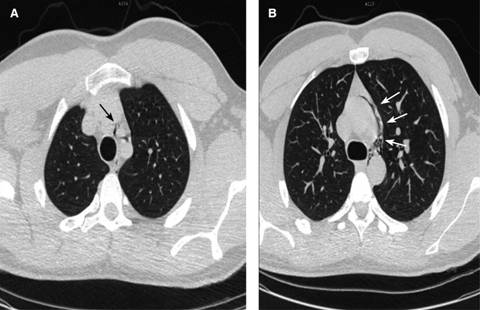

Masculino de 20 años, estudiante, con antecedentes de tabaquismo desde los 16 años (20 cigarrillos/semana), alcoholismo ocasional, deporte tres horas/semana; negó alergias y toxicomanías. Acudió a urgencias manifestando dolor retroesternal moderado, transfictivo, que se irradiaba a la zona interescapular y se incrementaba con la inspiración, de presentación inmediata tras un acceso de tos al momento de levantarse de la cama. Refirió disfagia moderada a la ingestión de líquidos y sólidos. A la exploración: estatura 1.85 m; peso 87 kg; IMC 25.42; FC 85 lat./min; FR 18/min; TA 120/80; Temp. 36.6 oC; cráneo: cara normal; cuello normal sin ingurgitación yugular; tórax con ampliación y amplexación normales; ruidos cardiacos rítmicos acompañados de un crujido áspero sincrónico con el ritmo cardiaco, localizado en todos los focos cardiacos, siendo de mayor intensidad en decúbito lateral derecho (signo de Hamman); los campos pulmonares, con murmullo vesicular normal; el dolor se exacerbaba a la inspiración profunda; abdomen y extremidades normales. Se efectuó un electrocardiograma (normal) y troponina cardiaca seriada a las cuatro y seis horas (siendo indetectable). La tomografía de tórax (Figuras 1 y 2) mostró presencia de aire entre el tronco braquiocefálico y emergencia de la carótida común izquierda y en la ventana aortopulmonar, se extendía caudalmente en íntimo contacto con la aorta descendente y se proyectaba a los vasos supraaórticos (efecto Macklin). Se practicó tránsito esofágico (normal). Con el diagnóstico de neumomediastino espontáneo, se le manejó con reposo, evitando maniobras de Valsalva; se prescribió paracetamol a dosis de 500 mg/TID y oxígeno, tres litros/min por 72 horas. Fue dado de alta asintomático a los cinco días de hospitalización; el signo de Hamman desapareció.

Figura 1: Tomografía computada con ventana para pulmón, cortes axiales (A y B) que muestran aire que se proyecta a los vasos supraaórticos (flechas); parénquima pulmonar sin evidencia de alteración estructural. Diagnóstico: Neumomediastino espontáneo provocado por un acceso de tos en masculino de 20 años de edad.